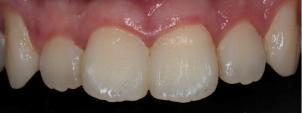

根管治疗+全冠修复后:

根管治疗后牙冠重新粘接: